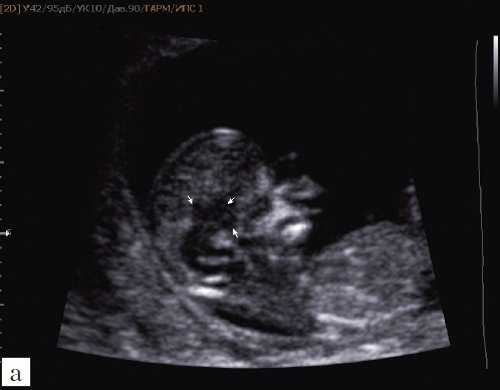

При изучении анатомии головного мозга плода в режиме 2D с применением стандартных аксиальных срезов во всех наших случаях мозжечок выглядел в виде овального образования однородной структуры с поперечным размером, менее уровня 5 процентиля для соответствующего срока беременности. При этом отсутствовала межполушарная выемка и область повышенной эхогенности по срединной линии мозжечка, характерная для отражения червя (рис. 1). На коронарном срезе также обращала внимание округлая однолобарная форма гипоэхогенного мозжечка (рис. 2). Использование трансвагинального подхода позволяло визуализировать дополнительно волокнистые структуры субарахноидального пространства (рис. 2).

Рис. 1. Аксиальные срезы головного мозга плода. Отражена картина однолобарного гипоплазированного мозжечка во всех наблюдениях.

а) Наблюдение 1.

б) Наблюдение 2.